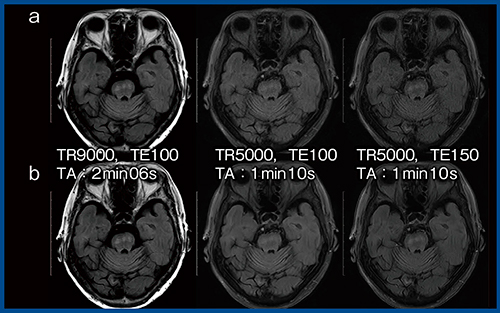

2.AiCEの活用

FLAIRは撮像に時間がかかるため,短縮が可能か検討を行った(図3)。TR/TE=5000ms/100msではT1コントラストが大幅に低下し,橋の淡い異常信号が消失する(図3 a中央)。それを,T2で補うためにTE=150msとしたところ,コントラストは改善するものの,全体の信号が低下するため粒状性が低下した(図3 a右)。そこで,AiCEを適用すると,SNRの改善とともに視覚的にも粒状性が改善し,1分10秒の撮像でも診断に耐えうる画像となった(図3 b右)。

図3 AiCEによるFLAIRの撮像時間の短縮(多発性硬化症)

a:AiCEなし b:AiCEあり